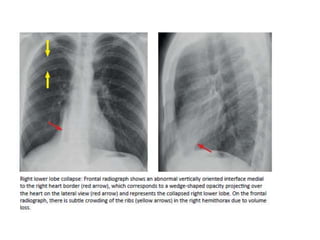

COLLAPSE

• Direct signs of atelectasis are from lobar volume loss

and include:

-Displacement of the fissures

-Vascular crowding.

• Indirect signs of atelectasis are due to the effect of

volume loss on adjacent structures

-Elevation of the diaphragm.

-Rib crowding on the side with volume loss.

-Mediastinal shift to the side with volume loss.

-Overinflation of adjacent or c/l lobes

-hilar displacement

COLLAPSE • Direct signsof atelectasis are from lobar volume loss and include: -Displacement of the fissures -Vascular crowding. • Indirect signs of atelectasis are due to the effect of volume loss on adjacent structures -Elevation of the diaphragm. -Rib crowding on the side with volume loss. -Mediastinal shift to the side with volume loss. -Overinflation of adjacent or c/l lobes -hilar displacement